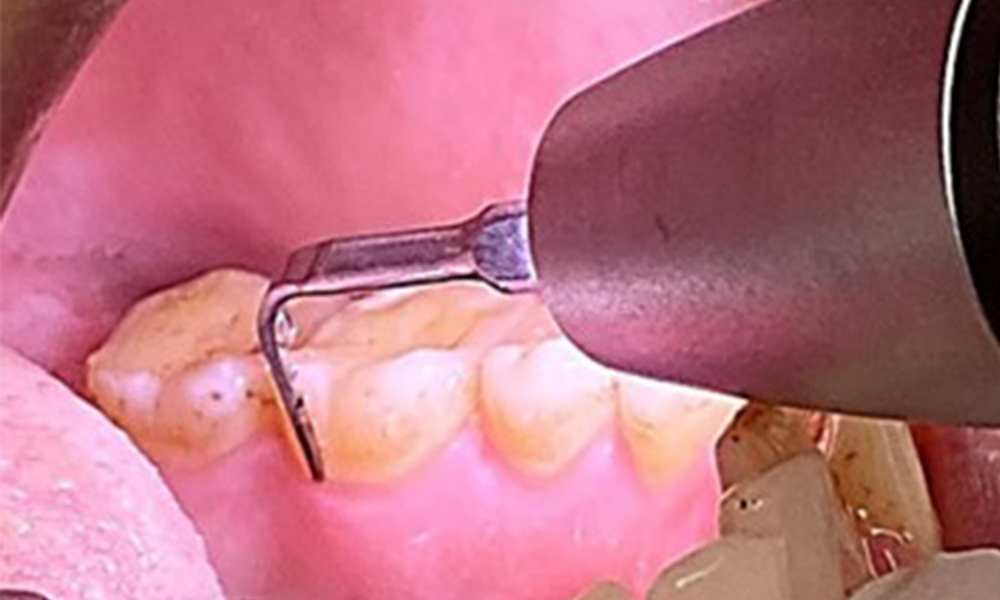

Instruction and motivation are important components of these appointments. Good home-based intraoral hygiene behaviour and understanding are important for patients. Plaque accumulation is particularly evident in the cervical regions (Fig. 8).

These must be discussed with the patient, and improvements to the teeth-brushing technique must be practised. A soft toothbrush attachment is recommended for home-based intraoral hygiene due to the presence of erosions and attritions.